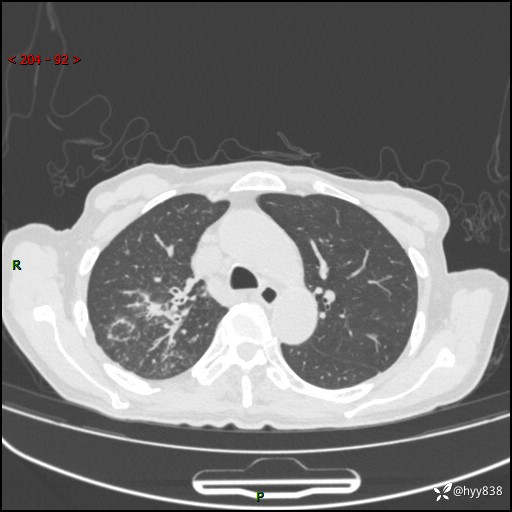

一个月后第二次CT检查(常规抗感染,患者不配合:增强、住院---)